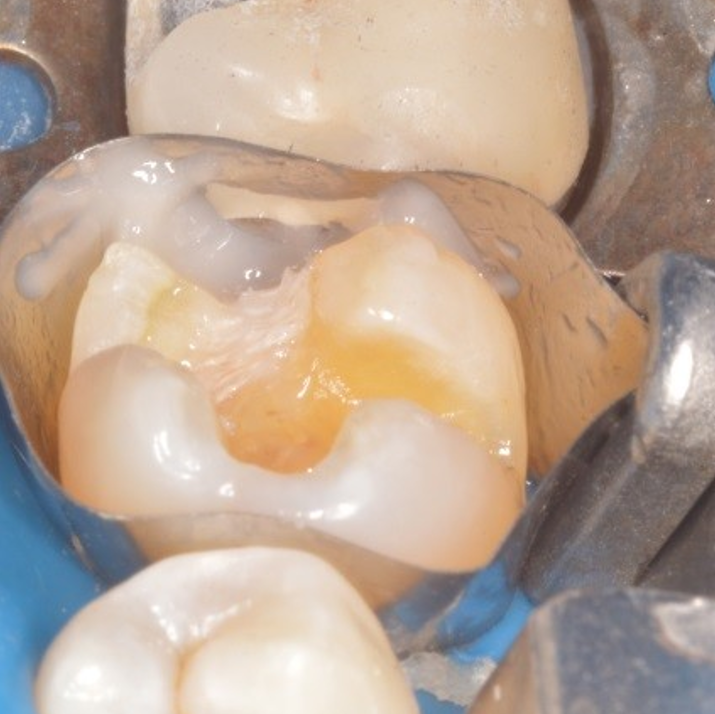

(A) Clinical presentation of a mandibular right second molar (31) with Distal Lingual Cusp Fracture Occlusal, lingual and distal/proximal views of a. A fractured cusp rarely damages the pulp, and usually doesn’t cause much pain. Craze line, fractured cusp, cracked tooth, split tooth, and vertical root fracture. When a piece of a tooth’s chewing surface breaks off, often around a filling, it’s called a fractured cusp. A fractured cusp molar no pain is a type. Distal Lingual Cusp Fracture.

Emergency treatment of a fractured molar Distal Lingual Cusp Fracture Your dentist can place a new filling or crown over the damaged tooth to protect it. The most common cuspal areas to fracture are the lingual cusps of the lower molars and the buccal cusps of the upper molars. The fracture originates on the occlusal surface and. When a piece of a tooth’s chewing surface breaks off, often around a. Distal Lingual Cusp Fracture.